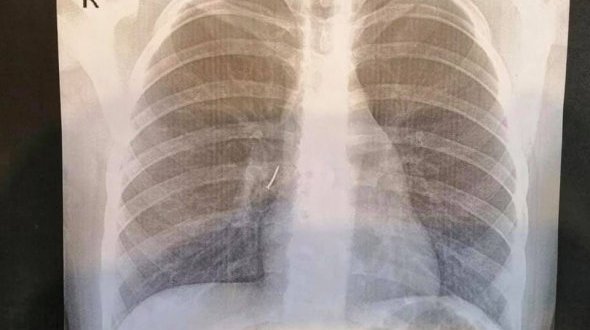

11-річна дівчинка проковтнула цвях

На Львівщині 11-річна дівчинка під час прогулянки з подругами проковтнула канцелярський цвях. Він застряг у бронхах. 21 листопада хірурги Львівської обласної дитячої лікарні ОХМАТДИТ її терміново […]